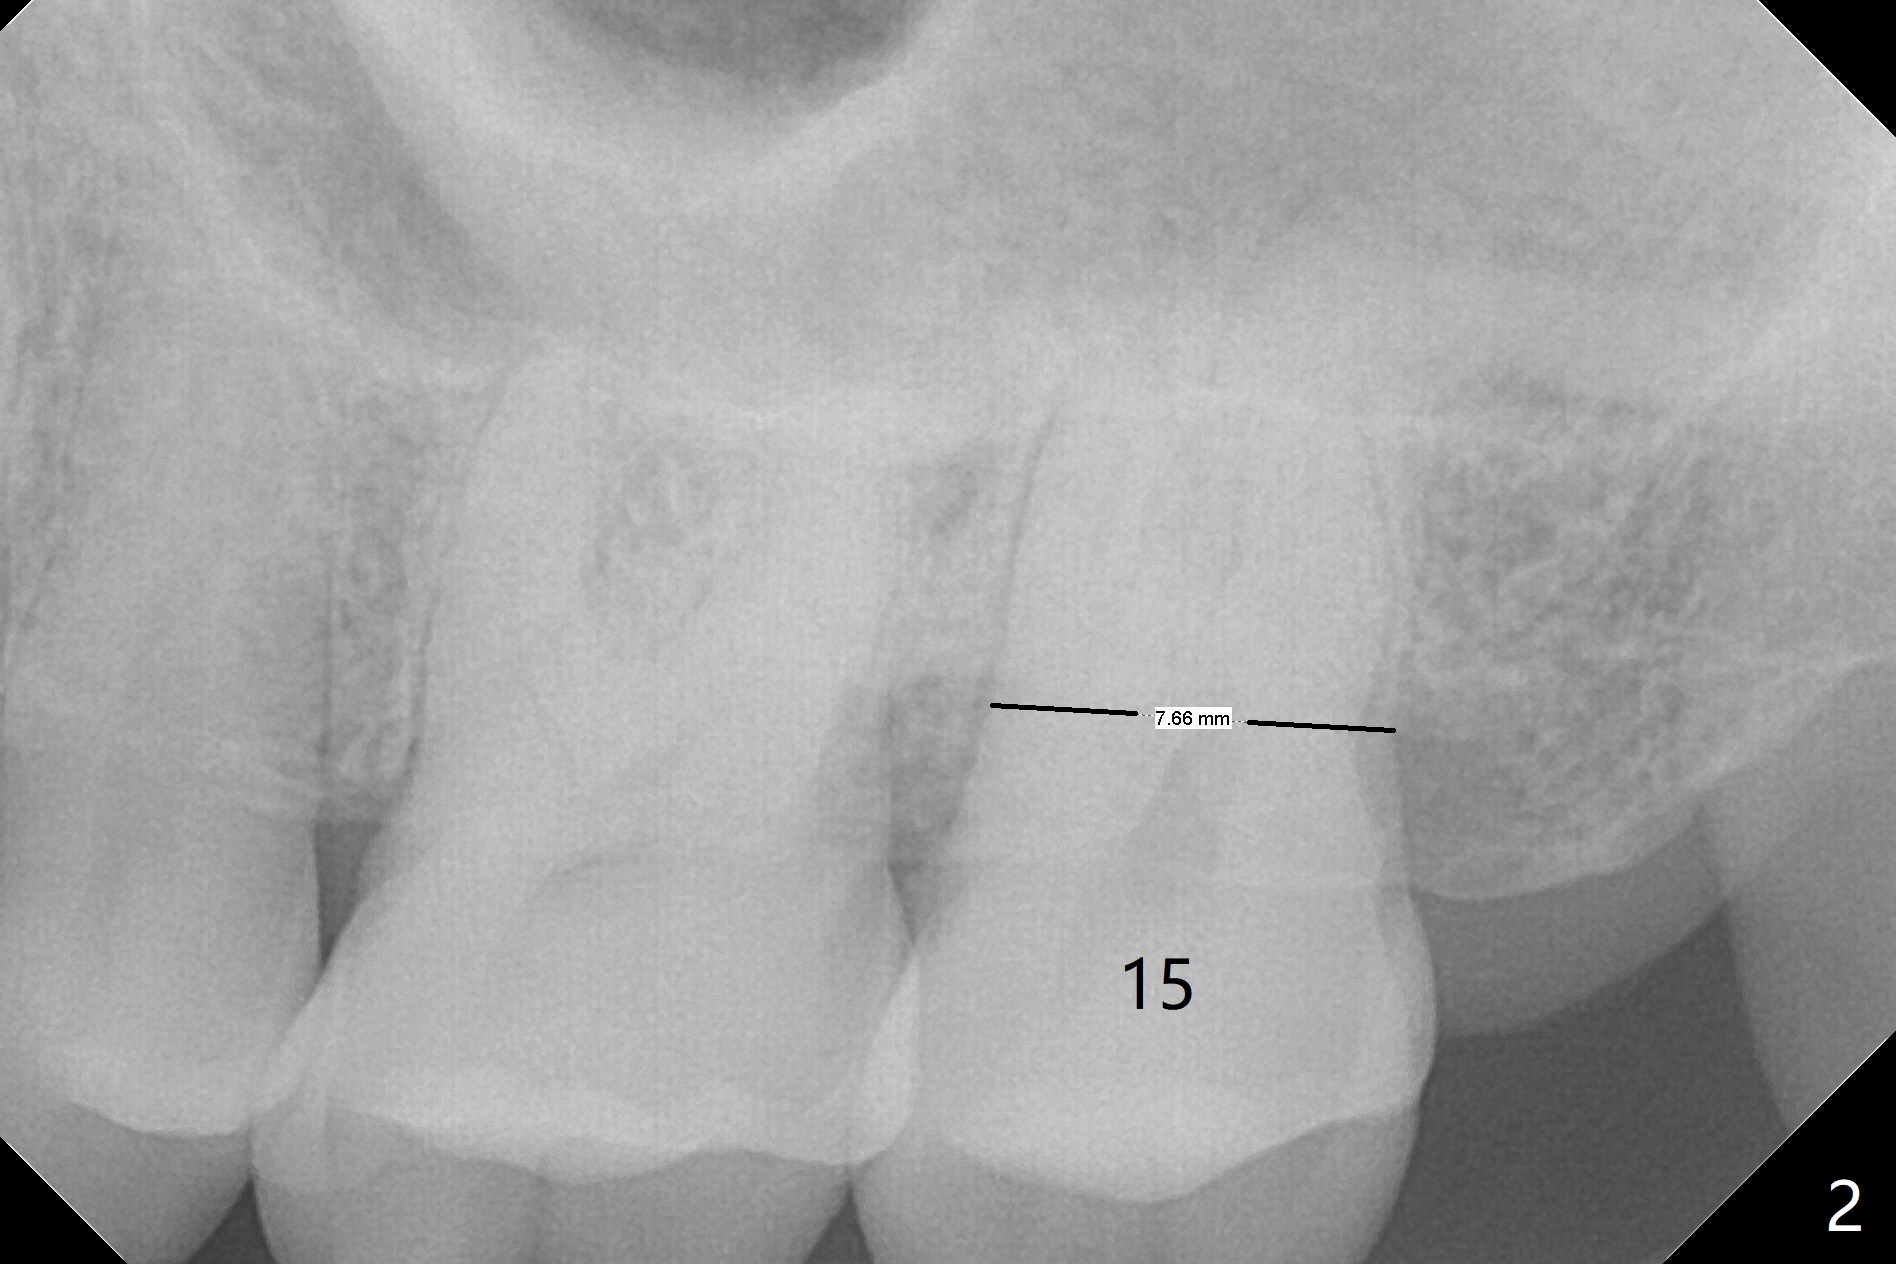

Initially the patient is reluctant to have the crack tooth extracted (Fig.1). Blood drawing for PRF fails. After extraction, the septum is confirmed to be short and thin. The bone density is moderate. When a 3.5 mm drill is being used, the osteotomy perforates into the mesiobuccal socket. A 5x10 mm IS implant achieves minimal stability. As 5.5, 6.0 and 7.0 mm cortical taps are inserted, primary stability is not obtained, as more bone is being removed at the level of the septum. When a 7x17 mm Tatum tapered tap is placed, it looks too small for the socket, as confirmed by measurement of a preop PA (Fig.2). Chronic infection associated with crack syndrome for 2 years may cause bone loss of the socket walls. Since the primary stability of a 8x17 mm tapered tap is not high (Fig.3), a 8x14 mm cylindrical implant is placed (after try in of its dummy one) with > 50 Ncm (Fig.4). The implant engages into the mesial and distal socket walls for stability. A 6x3 mm abutment is placed for an immediate provisional. In spite of difficult manipulation, the sinus membrane remains intact. Vanilla graft is placed for sinus lift and buccal and palatal gaps. Since IS implants are more or less cylindrical and if a 5 mm one does not achieve primary stability, a larger Tatum tapered tap should be tried immediately without using IS cylindrical taps. The patient returns 3 months postop, requesting early restoration before a trip to home country. The provisional has occlusal perforation. Final restoration is cemented nearly 4 months postop (Fig.5,6). The large implant makes the early restoration possible. However there is bleeding on probing palatal 1.5 years post cementation (Fig.7), suggesting palatal thread exposure. Return to Upper Molar Immediate Implant, Prevent Molar Periimplantitis (Protocols, Table), Armaments 6 Xin Wei, DDS, PhD, MS 1st edition 05/07/2018, last revision 05/08/2021